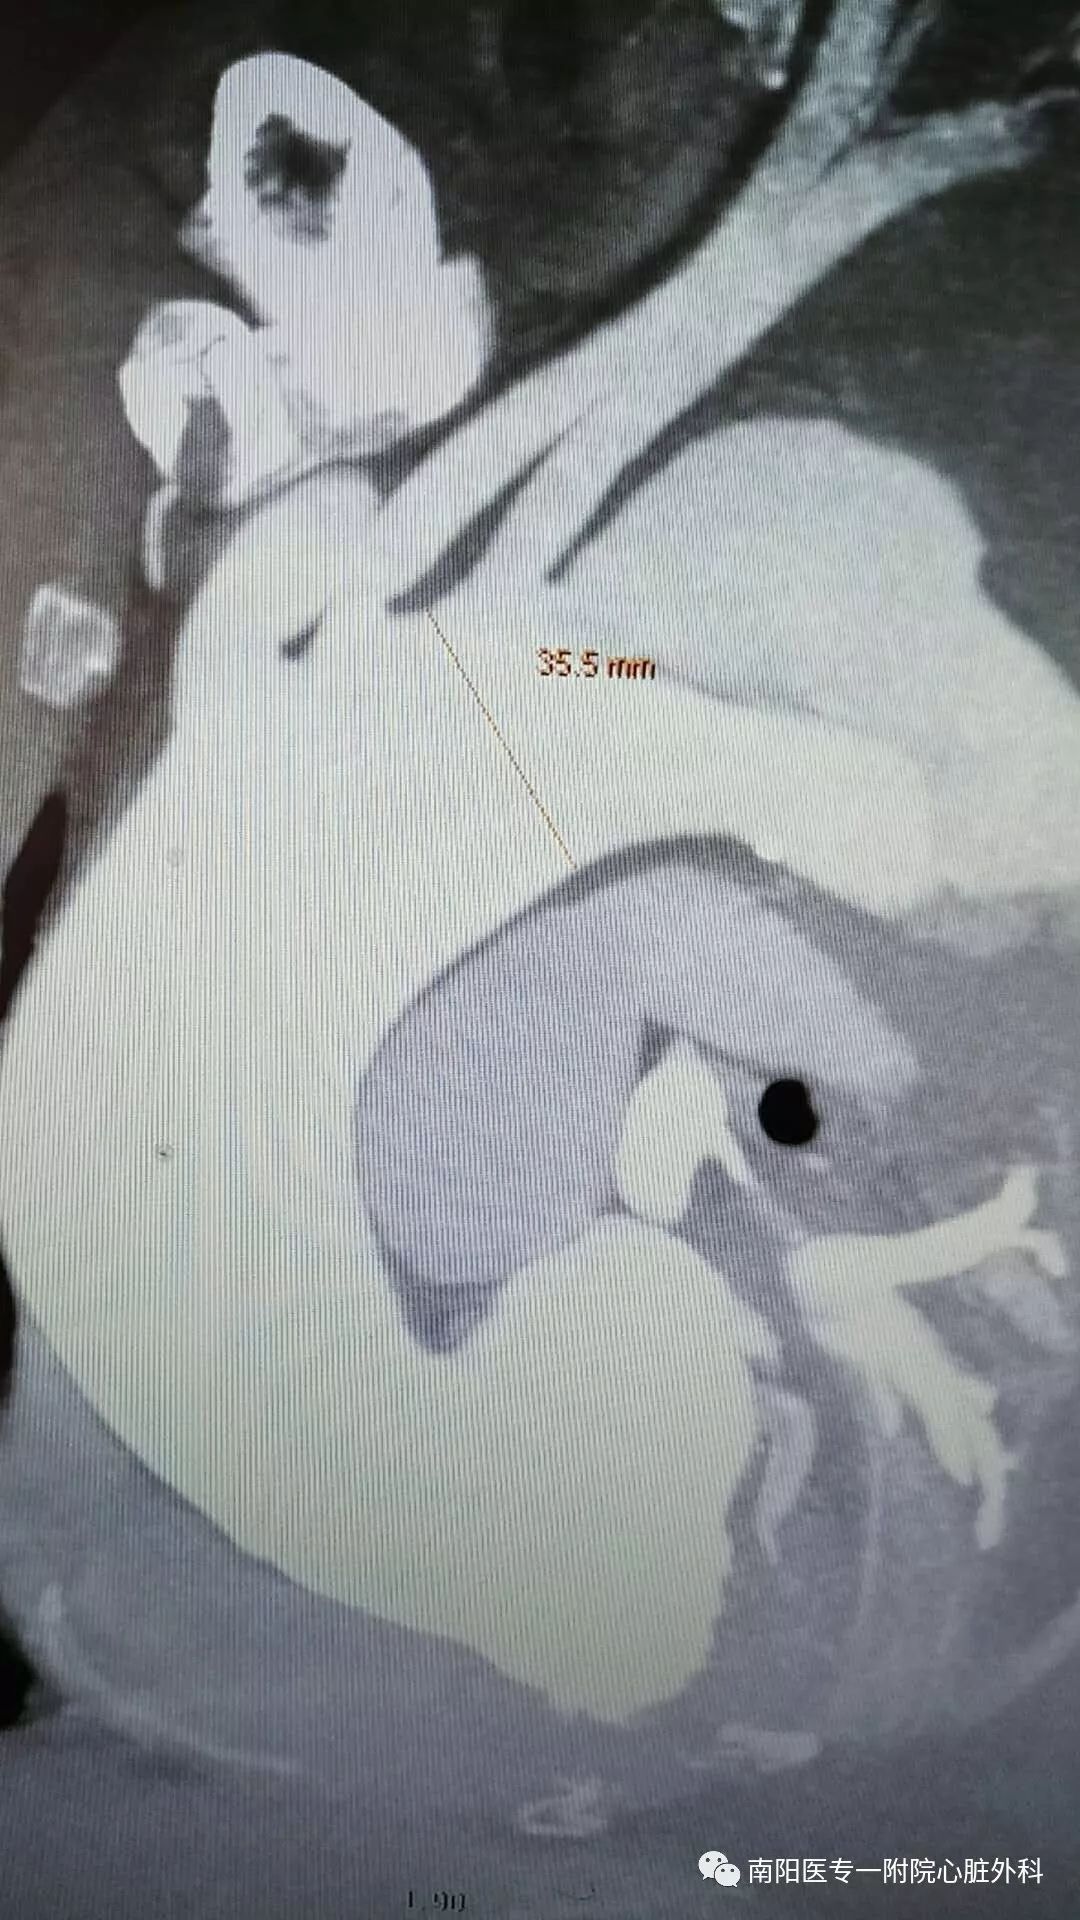

立即行CTA,明确诊断为Stanford B 型主动脉夹层,破口位于左锁骨下动脉根部,并且主动脉弓部明显增宽,左侧胸腔大量积液。此种情况非常危险,为主动脉夹层濒临破裂的征象,随时有发生破裂死亡的可能。

由于患者主动脉弓支架锚定区直径近36mm,需要大型号的支架,整个南阳市内没有,经联系只有郑州有,大雪封路,没有班车及快递,马上启动应急预案,连夜从郑州坐火车把支架运回,在住院第二天上午急诊手术,行腋腋动脉转流+主动脉覆膜支架植入+左锁骨下动脉弹簧圈封堵术,术后患者恢复顺利。